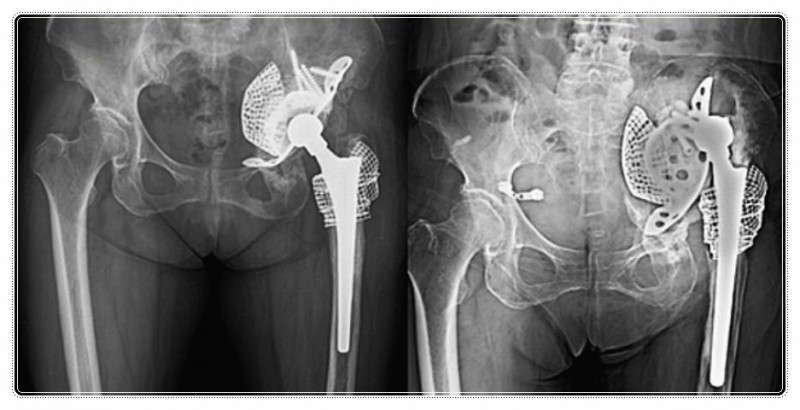

우리 몸의 고관절은 건물을 지탱하는 튼튼한 주춧돌과 같습니다.

지금은 그 주춧돌이 조금 낡거나 금이 가서 새것으로 교체한 상황이에요.

그 후에 그 주춧돌을 감싸고 있는 흙이 단단히 다져지지 않고, 주변 기둥들이 기울어져 있다면, 건물은 다시 흔들릴 수밖에 없죠.

그래서 수술은 주춧돌을 교체하는 과정이라면, 재활은 그 주변의 흙을 다지고 기둥의 수평을 맞추는 매우 중요한 작업입니다.